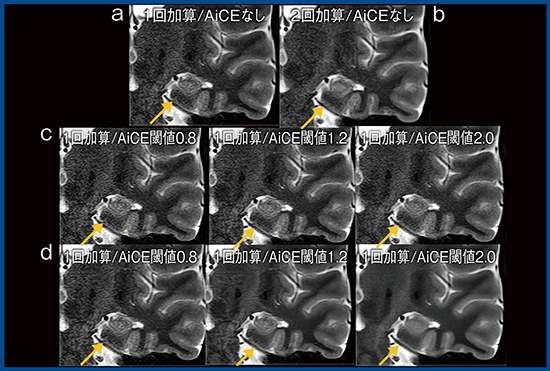

図1は,AiCEの有無による冠状断像の比較であるが,50秒で撮像した1回加算の画像(a)に対して,AiCEを適用し強度と閾値を調節している(c,d)。強度5,閾値1.2の画像(図1 d中央)は視認性がきわめて良好である。ただし,AiCEは高周波成分のノイズ除去を行うため1),脳脊髄液の拍動のアーチファクトなどは残存する。また,2回加算の画像(図1 b)で描出されている嗅内野皮質(↑)は,1回加算ではAiCEを適用しても不明瞭である(図1 c,d)。元画像で見えないものは,AiCEを適用しても見えるようにはならないことを理解して,適切に用いることが重要である。

図1 AiCEによるT2強調冠状断像の撮像時間短縮

a:1回加算/AiCEなし b:2回加算/AiCEなし

c:1回加算/AiCE強度1 d:1回加算/AiCE強度5